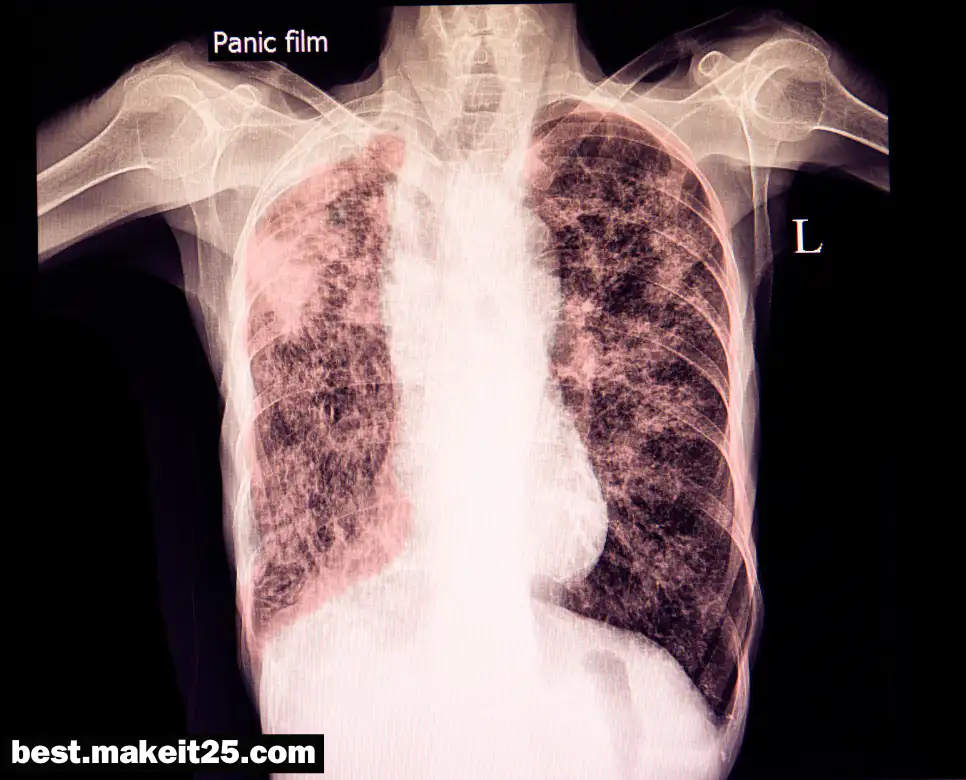

‘IPF’는 Idiopathic Pulmonary Fibrosis, 즉 특발성 폐섬유증을 의미합니다. 이는 원인이 명확하지 않은 폐의 만성 질환으로, 폐의 조직이 염증과 섬유화되어 딱딱하고 탄력이 없어지는 것을 말합니다. IPF는 간질성 폐질환(ILD)의 한 종류로 분류되며, 폐의 간질조직에 만성적인 염증 반응이 일어나 폐 조직이 점차 섬유화되고 경화되는 진행성 질환입니다.

- 호흡 기능: 폐의 섬유화로 인해 호흡 기능이 저하되고, 산소 교환 능력이 감소합니다.

- 증상: 호흡곤란, 마른 기침, 피로감, 체중 감소, 청색증이나 곤봉지 같은 증상을 보일 수 있습니다.

- 진단: 고해상도 CT를 촬영하면 생검없이 90%의 정확도로 진단이 가능합니다. 폐기능검사에서는 제한성 타입을 보이는 질환입니다.

- 치료: 현재까지 특별한 치료법은 없으나, 일부 약물이 증상을 호전시키는 데에 효과적일 수 있습니다.

IPF는 치명적인 폐질환으로, 폐 간질조직의 섬유증이 지속적으로 진행되는 특징을 가집니다. 이 질환은 환자의 삶의 질과 생존율에 큰 영향을 미치므로, 적절한 진단과 관리가 필수적입니다.